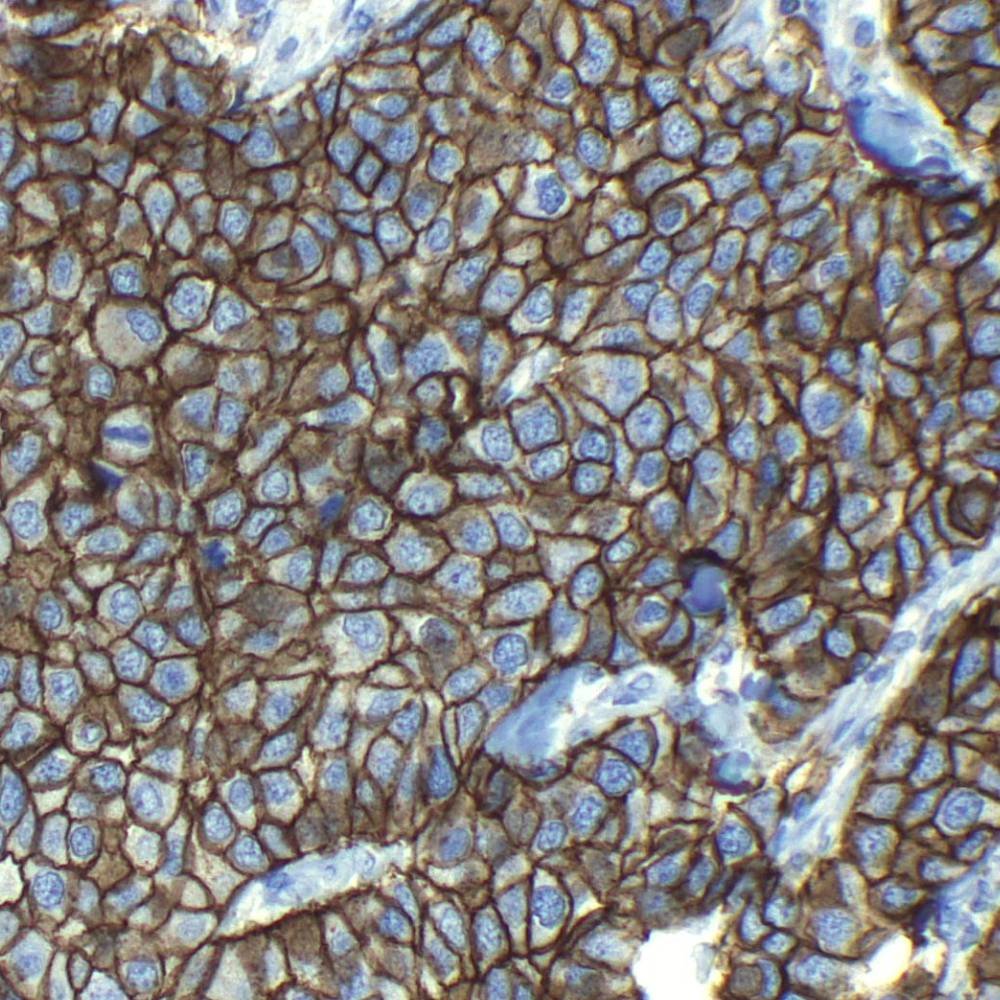

HER2/ErB2 is one of the four members of the ErbB receptor family of transmembrane receptor-like tyrosine kinase. The kinase activity of ErbB2 can be activated without a ligand if it is overexpressed, and by association with other ErbB proteins. Overexpression of ErbB2 is detected in almost 40% of human breast cancers.